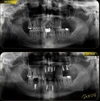

الصور